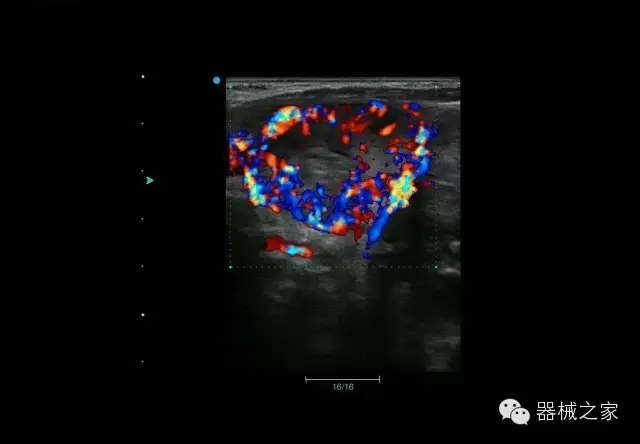

經(jīng)典產(chǎn)品:Apogee 1000

臨床圖片賞析

結(jié)甲

腎臟血流

肝血管瘤

產(chǎn)品特點(diǎn)

·屏幕可左右90度旋轉(zhuǎn);

·雙模操控;

·兩用提手;

·雙鋰電池;

·超輕機(jī)身;

·15寸高亮高清醫(yī)學(xué)顯示器;

·衛(wèi)星布局操控面板;

·一體化剪切板;

·多功能導(dǎo)航鍵;

“宏云”平臺

·采用移植自高端臺式彩超的“宏云”平臺技術(shù),使系統(tǒng)具有更優(yōu)秀的圖像效果;

人性化的設(shè)計(jì)

·內(nèi)置電池,輕巧的外觀設(shè)計(jì)以及臨床功能、軟硬件設(shè)計(jì)的人性化設(shè)計(jì),使系統(tǒng)在臨床多科室移動診查中,均從容應(yīng)對;

Fusion THI二代融合諧波成像

·在不同諧波頻率段獲得的信息進(jìn)行實(shí)時融合,既能獲得諧波圖像分辨率又能提高圖像的穿透力,降低圖像噪音;

XBeam多域復(fù)合成像

·通過頻域和空域角度進(jìn)行復(fù)合的圖像處理,能有效消除由于圖像離散化和圖像衰減引起的空間分辨率下降的不利影響,彌補(bǔ)原有圖像空間分辨率的不足,獲得更加清晰的圖像;

CFDA注冊證編號

·粵食藥監(jiān)械(準(zhǔn))字2014第2231316號